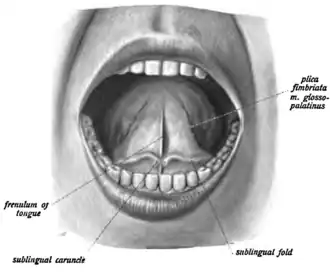

The frenulum (or frenum) of the tongue, tongue web, lingual frenulum, frenulum linguae, or fraenulum[1] is a small fold of mucous membrane extending from the floor of the mouth to the midline of the underside of the human tongue.

The thin strip of tissue that runs vertically from the floor of the mouth to the undersurface of the tongue is called the lingual frenulum. It tends to limit the movement of the tongue, and in some people, it is so short that it actually interferes with speaking.

A hump of tissue near the base of the tongue houses a series of saliva gland ducts. The two largest ducts are called Wharton's Ducts and they empty the submandibular (submaxillary) and sublingual salivary glands into a small prominence on either side of the frenulum, the sublingual caruncle. These ducts can be quite active in some persons, and upon occasion, a considerable amount of saliva may erupt from them while talking, eating, yawning, or cleaning the teeth in a process known as gleeking. The sublingual saliva glands empty through a series of tiny ducts in the tissue on either side of Wharton's ducts. The tongue is attached to the floor of the oral cavity by the frenulum.